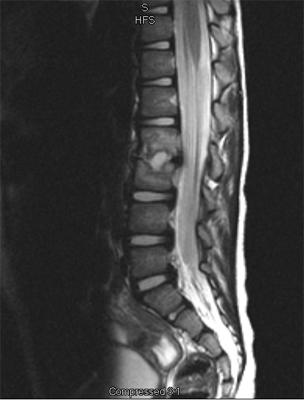

An MRI may be required if further examination of the spine is needed. An MRI machine uses magnetic waves, not X-rays, to show the soft tissues of the body. These tissues include the spinal cord, nerves, and discs. It can also evaluate spinal bones. An MRI allows your healthcare professional to look at slices of the area in question. The test may require the use of dye in an IV. Sedation or anesthesia may be needed to help your child lie still for this test.

In the early stage of the injury an X-ray may not show a fracture. Special imaging tests such as magnetic resonance imaging (MRI), computed tomography scans (CT), or a bone scan may show signs of a stress fracture. Spondylolysis may cause pain in a particular spot in the low back and spasm of the muscles along the spine. Often it will cause pain into the buttocks or thighs. Spondylolysis will often heal with the appropriate rest, a change in activity levels, and by avoiding hyperextension and rotation of the spine. Bracing may be helpful if symptoms do not get better.